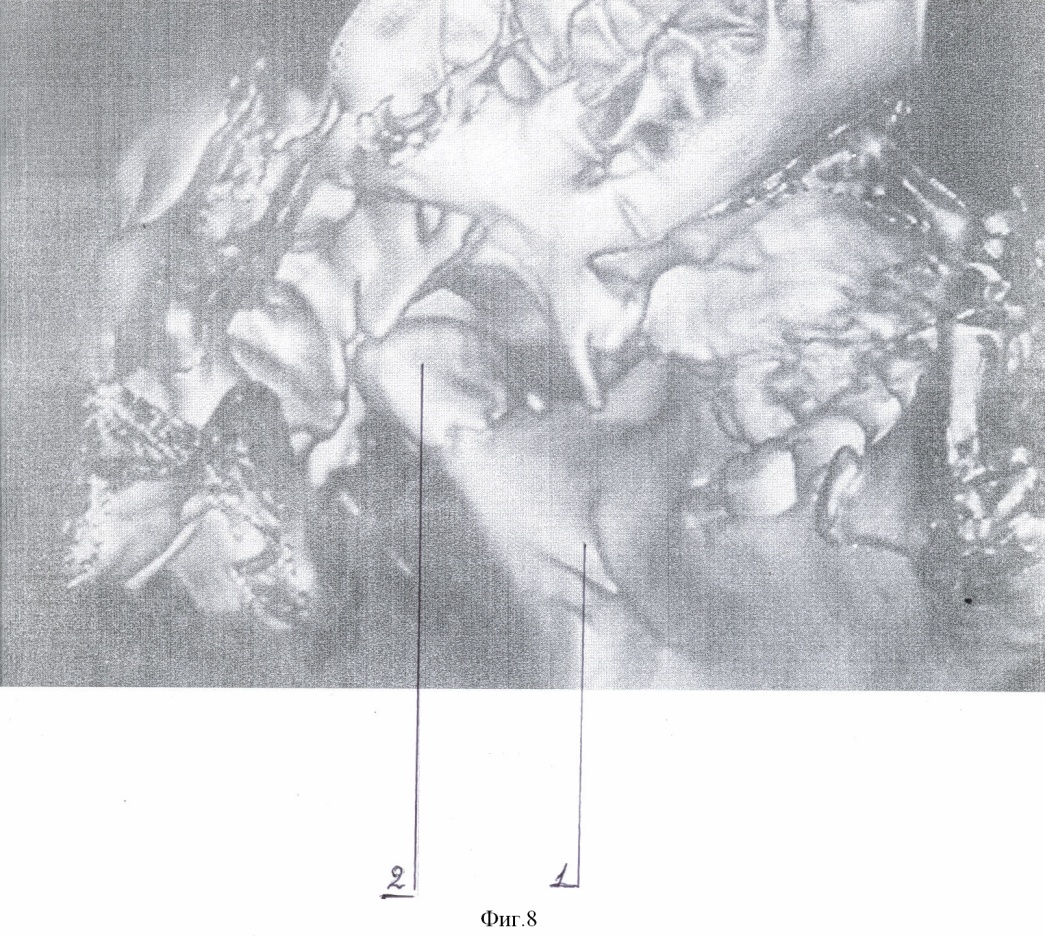

Способ осуществляют следующим образом. Типичным доступом через разрез кожи в подчелюстной области, окаймляющим угол нижней челюсти, осуществляют послойный доступ к линии перелома поднадкостнечно по латеральной поверхности ветви. Вывихнутый диссектором малый фрагмент вместе с суставной капсулой выводят в вырезку. Суставную капсулу рассекают вперед на 0,3-0,5 см. Отломок суставного отростка освобождают от суставной капсулы и выводят из раны. Фиброзные наложения раневых поверхностей костей удаляют. После оценки состояния отломка к участку, свободному от суставной поверхности, по заднему краю фиксируют микропластину (Т, Н, Х, L, Y-образной формы). Свободный конец микропастины изгибают для плотного прилегания к большему фрагменту по задней и латеральной поверхности ветви. Из суставной капсулы формируют ложе в суставной впадине. Малый фрагмент с подготовленной микропластиной устанавливают в ложе в анатомическом положении. Суставную капсулу над суставным бугорком укрепляют узловыми швами ПДС 4/0. Большой фрагмент репонируют на установленную в ложе конструкцию. Свободный конец микропластины фиксируют к заднелатеральной поверхности большего фрагмента микрошурупами. Осуществление способа и результат продемонстрированы на чертежах 1-8: фиг.1 – компьютерная томограмма (реконструкция) нижней челюсти, левая боковая; фиг.2 – компьютерная томограмма (реконструкция) нижней челюсти, вид сзади; фиг.3 – компьютерная томограмма (реконструкция) нижней челюсти, вид косо сзади; фиг.4 – собранная конструкция, вид сзади; фиг.5 – собранная конструкция, вид спереди; фиг.6 – компьютерная томограмма (реконструкция), вид спереди, после операции; фиг.7 – компьютерная томограмма (реконструкция) нижней челюсти, левая боковая, после операции; фиг.8 – компьютерная томограмма (реконструкция) нижней челюсти, левый суставной отросток, вид изнутри, после операции: где 1 – нижняя челюсть, 2 – отломок суставного отростка, 3 – титановая микропластина, 4 – микрошуруп, 5 – дренажная трубка.

Пример. Больной П., 14 лет поступил в отделение челюстно-лицевой хирургии ДККБ 20.04.07 г. с диагнозом: травматический тройной перелом нижней челюсти; перелом – вывих головки суставного отростка слева, перелом суставной головки справа без смещения, косой центральный перелом тела нижней челюсти со смещением (фиг. 1, 2, 3). 23.04.07 г. под общим обезболиванием выполнено оперативное вмешательство – открытая репозиция, металлоостеосинтез суставной головки слева Т-образной микропластиной, открытая репозиция, металлоостеосинтез косого перелома тела нижней челюсти двумя параллельными минипластинами. Типичным доступом через разрез кожи в подчелюстной области слева, окаймляющим угол нижней челюсти 1, осуществлен послойный доступ к линии перелома поднадкостнечно по латеральной поверхности ветви нижней челюсти. При помощи диссектора малый фрагмент мобилизован и вывихнут в вырезку вместе с суставной капсулой. Суставная капсула рассечена вперед на 0,5 см. Отломок суставного отростка 2 освобожден от суставной капсулы и выведен наружу. Фиброзные наложения на раневых поверхностях фрагментов удалены. По заднему краю отломка, по поверхности, свободной от суставной, при помощи микрошурупов 4 фиксирована Т-образная титановая микропластина 3, изогнутая для плотного прилегания к заднелатеральной поверхности большего фрагмента (фиг. 4, 5). Суставная капсула перемещена и расправлена в суставной ямке. В образованное ложе уложена конструкция в анатомическом положении. На края суставной капсулы над суставным бугорком наложены 2 узловых шва ПДС 4/0, обеспечивающие плотный охват отломка. Больший фрагмент репонирован на установленную конструкцию. Свободный конец микропластины 4 после небольшой коррекции изгиба фиксирован к заднелатеральной поверхности большего фрагмента микрошурупами 3. Рана послойно ушита с оставлением активного дренажа 5. Подчелюстным разрезом осуществлен послойный доступ к линии перелома тела нижней челюсти. Произведена типичная репозиция костных отломков, остеосинтез двумя параллельными минипластинами. Рана послойно ушита.

В послеоперационном периоде проводилась иммобилизация челюсти при помощи шин Васильева с межчелюстными вытяжениями. На контрольно компьютерной томограмме (26.04.07 г., фиг. 6, 7, 8) выявлено удовлетворительное стояние костных отломков. Больной выписан 4.05.07 г на дальнейшее амбулаторное лечение.